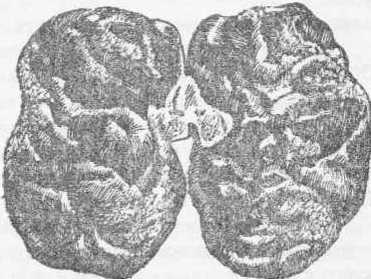

Болезнь почек со склеротическим поражением артериол, разрастанием соединительной ткани, атрофией паренхимы, нарушением мочеобразующей и выделительной функций, при этом почки уплотняются, структурно изменяются и сморщиваются (рис. 128).

Нефросклероз (нефроцирроз): неровная поверхность почек с множеством западающих беловатых участков